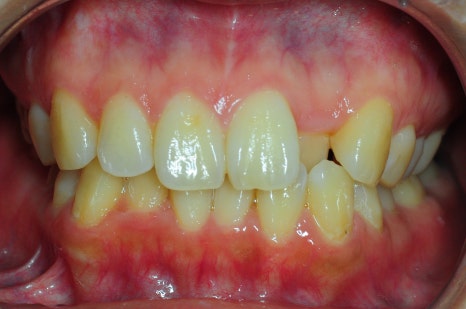

< 스마일디치과 비발치 교정 사례 >

*치료 전후 사진은 환자의 동의하에 게재하였으며, 동일한 환경과 조건에서 촬영된 전후 사진입니다.